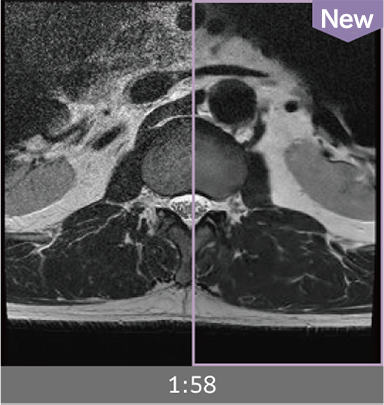

Combining high-speed imaging technology with Advanced Reconstruction enables shorter exams and reduces image noise.

Images can be obtained at high speed by combining two technologies: IP-RAPID, which reduces imaging time while maintaining image quality, and Advanced Reconstruction to improve image quality.

Under-sampling reduces imaging time, and iterative reconstruction with IP-RAPID reduces noise and artifacts.

In addition, Advanced Reconstruction further eliminates noise and produces images that are easier to use in making a diagnosis.